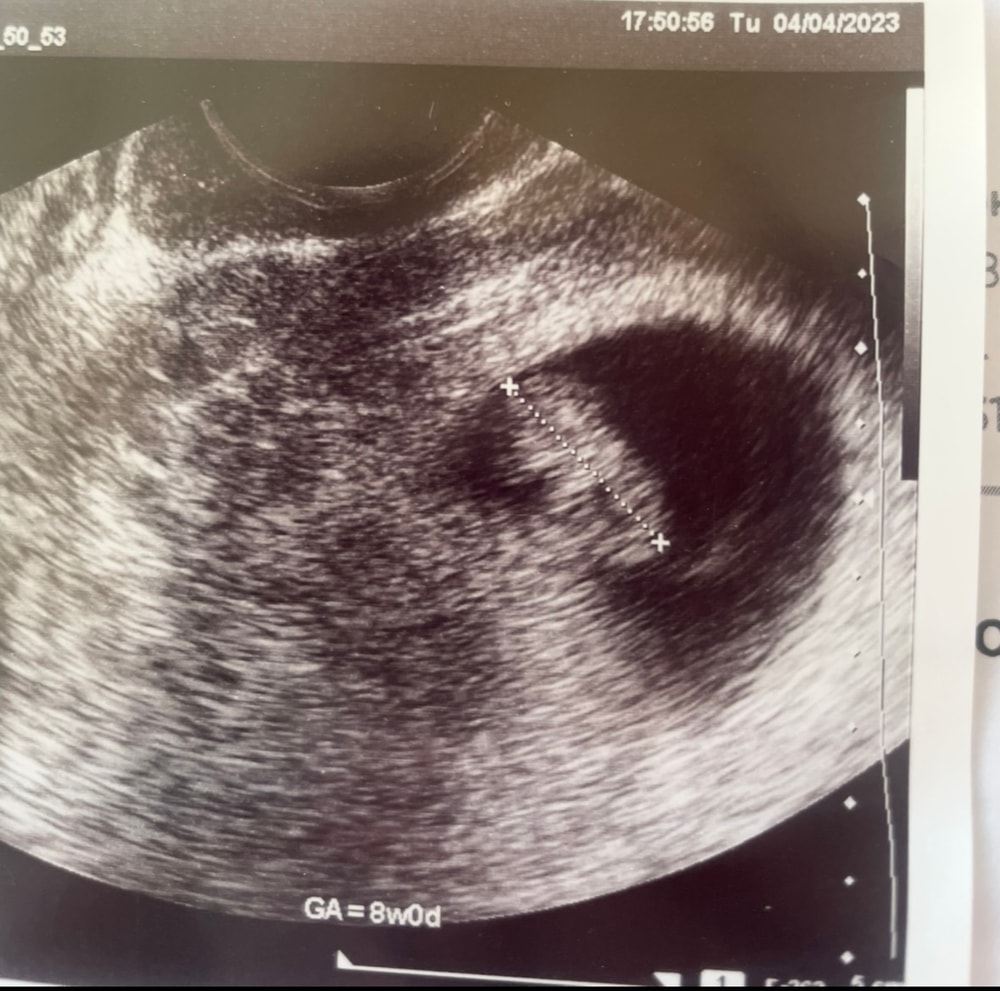

уже скоро можно сдать кро